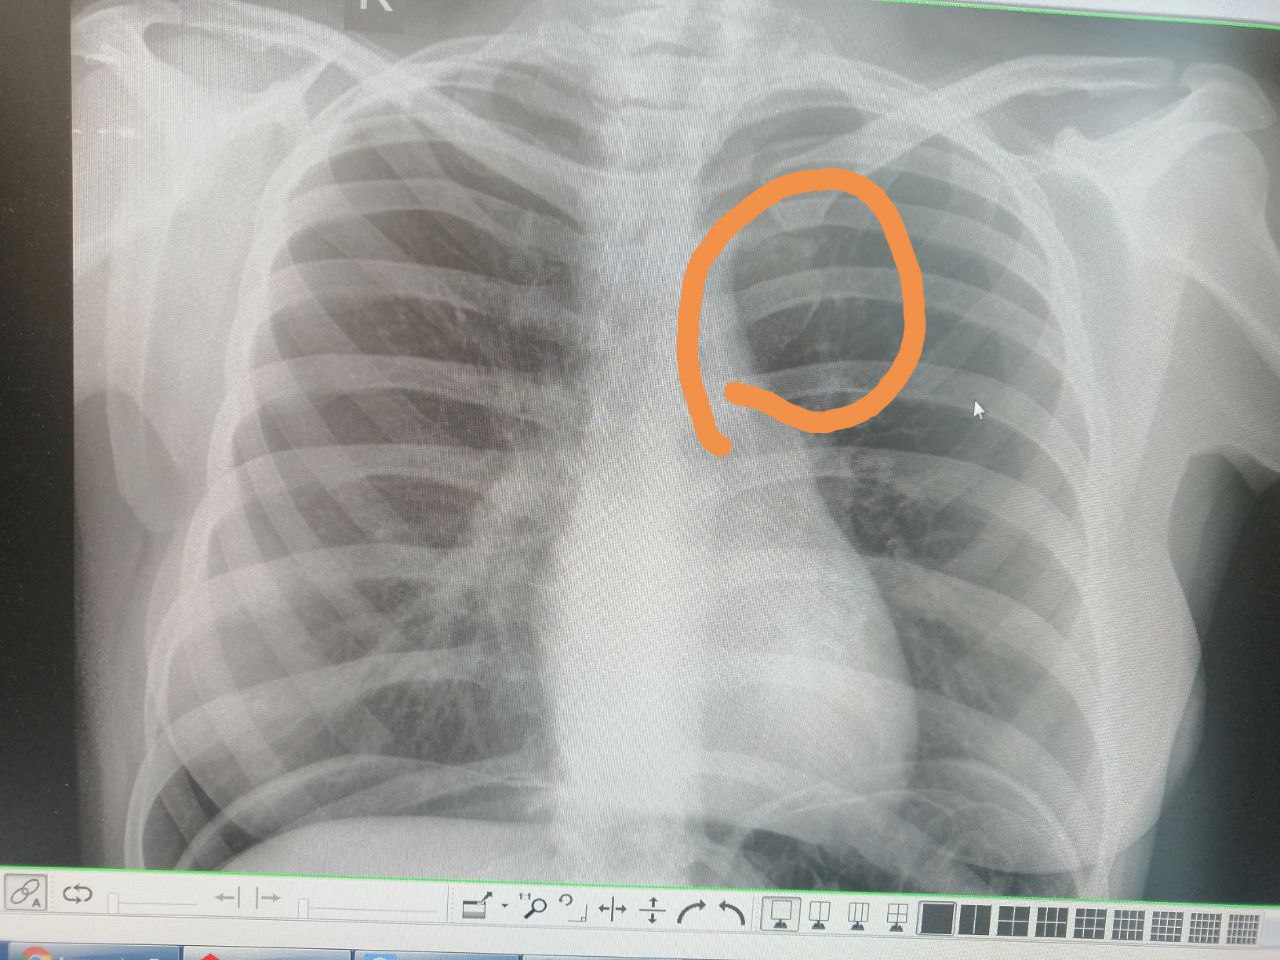

Женщина 50 лет. Короновирусная пневмония. Плюс, в легких вот такой округлый участок разрежения. Стоит ли как-то отдельно  ее обозначить?э

Кальций на фоне эмфиземы и фиброза?

Мне видится в центре небольшой бронхоэктазик забитый мокротой, вокруг по сути "воздушная ловушка"...